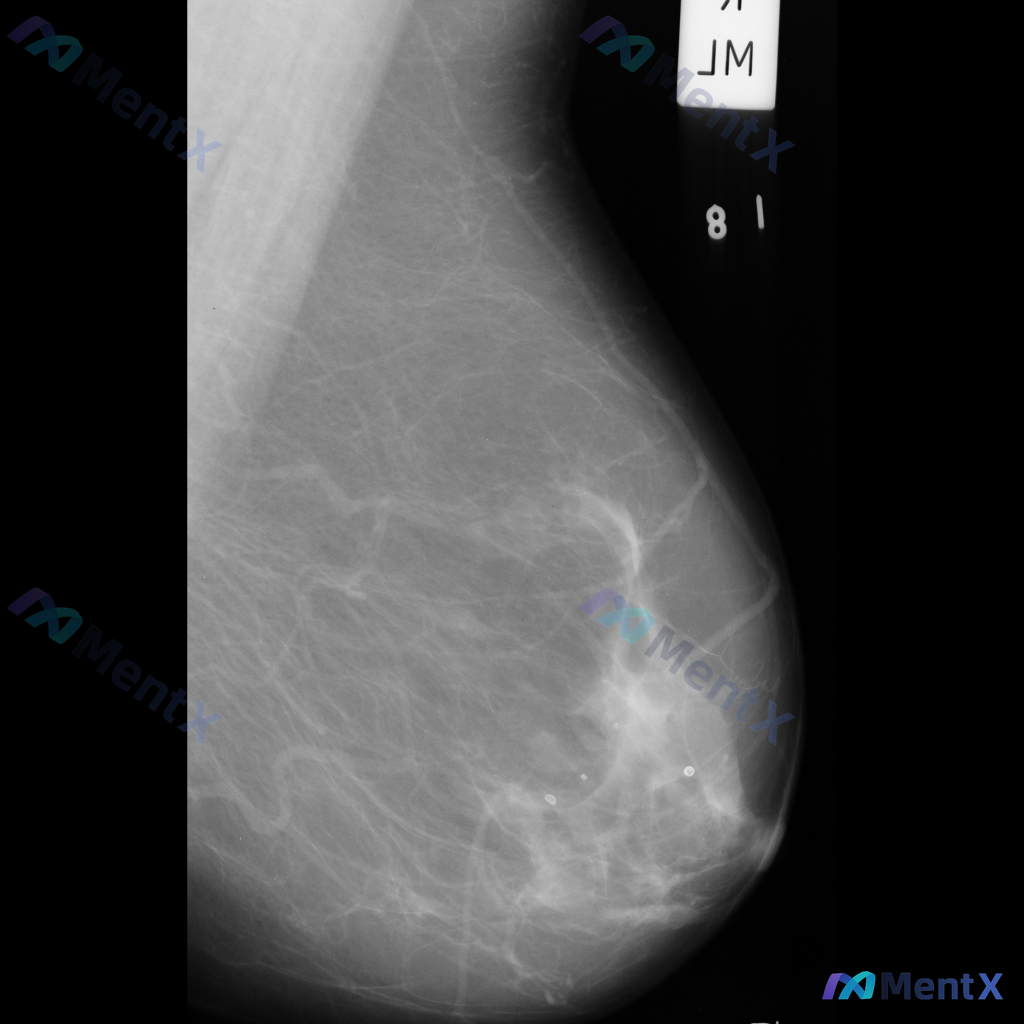

整理到一张乳腺钼靶的读片资料,想和大家一起讨论一下。 图像里能看到两处比较明确的异常: - 乳腺中下部有一个不规则、毛刺状的高密度肿块,周围还有结构扭曲的表现 - 乳腺上部还有一个类圆形的高密度肿块,形态相对规则一些 背景是不均匀致密型的乳腺组织。 单看这组图像表现,大家会优先往哪个方向考虑?

整理到一张乳腺钼靶影像资料,主要表现如下: - 乳腺内可见一个较大的肿块,形态不规则,边界部分模糊、呈毛刺状,密度较高,同时伴有明显的结构扭曲; - 另外还存在一枚较小的圆形、边界相对清晰的高密度结节。 想和大家讨论一下:单看目前这组影像表现,你会更倾向哪一种判断方向?